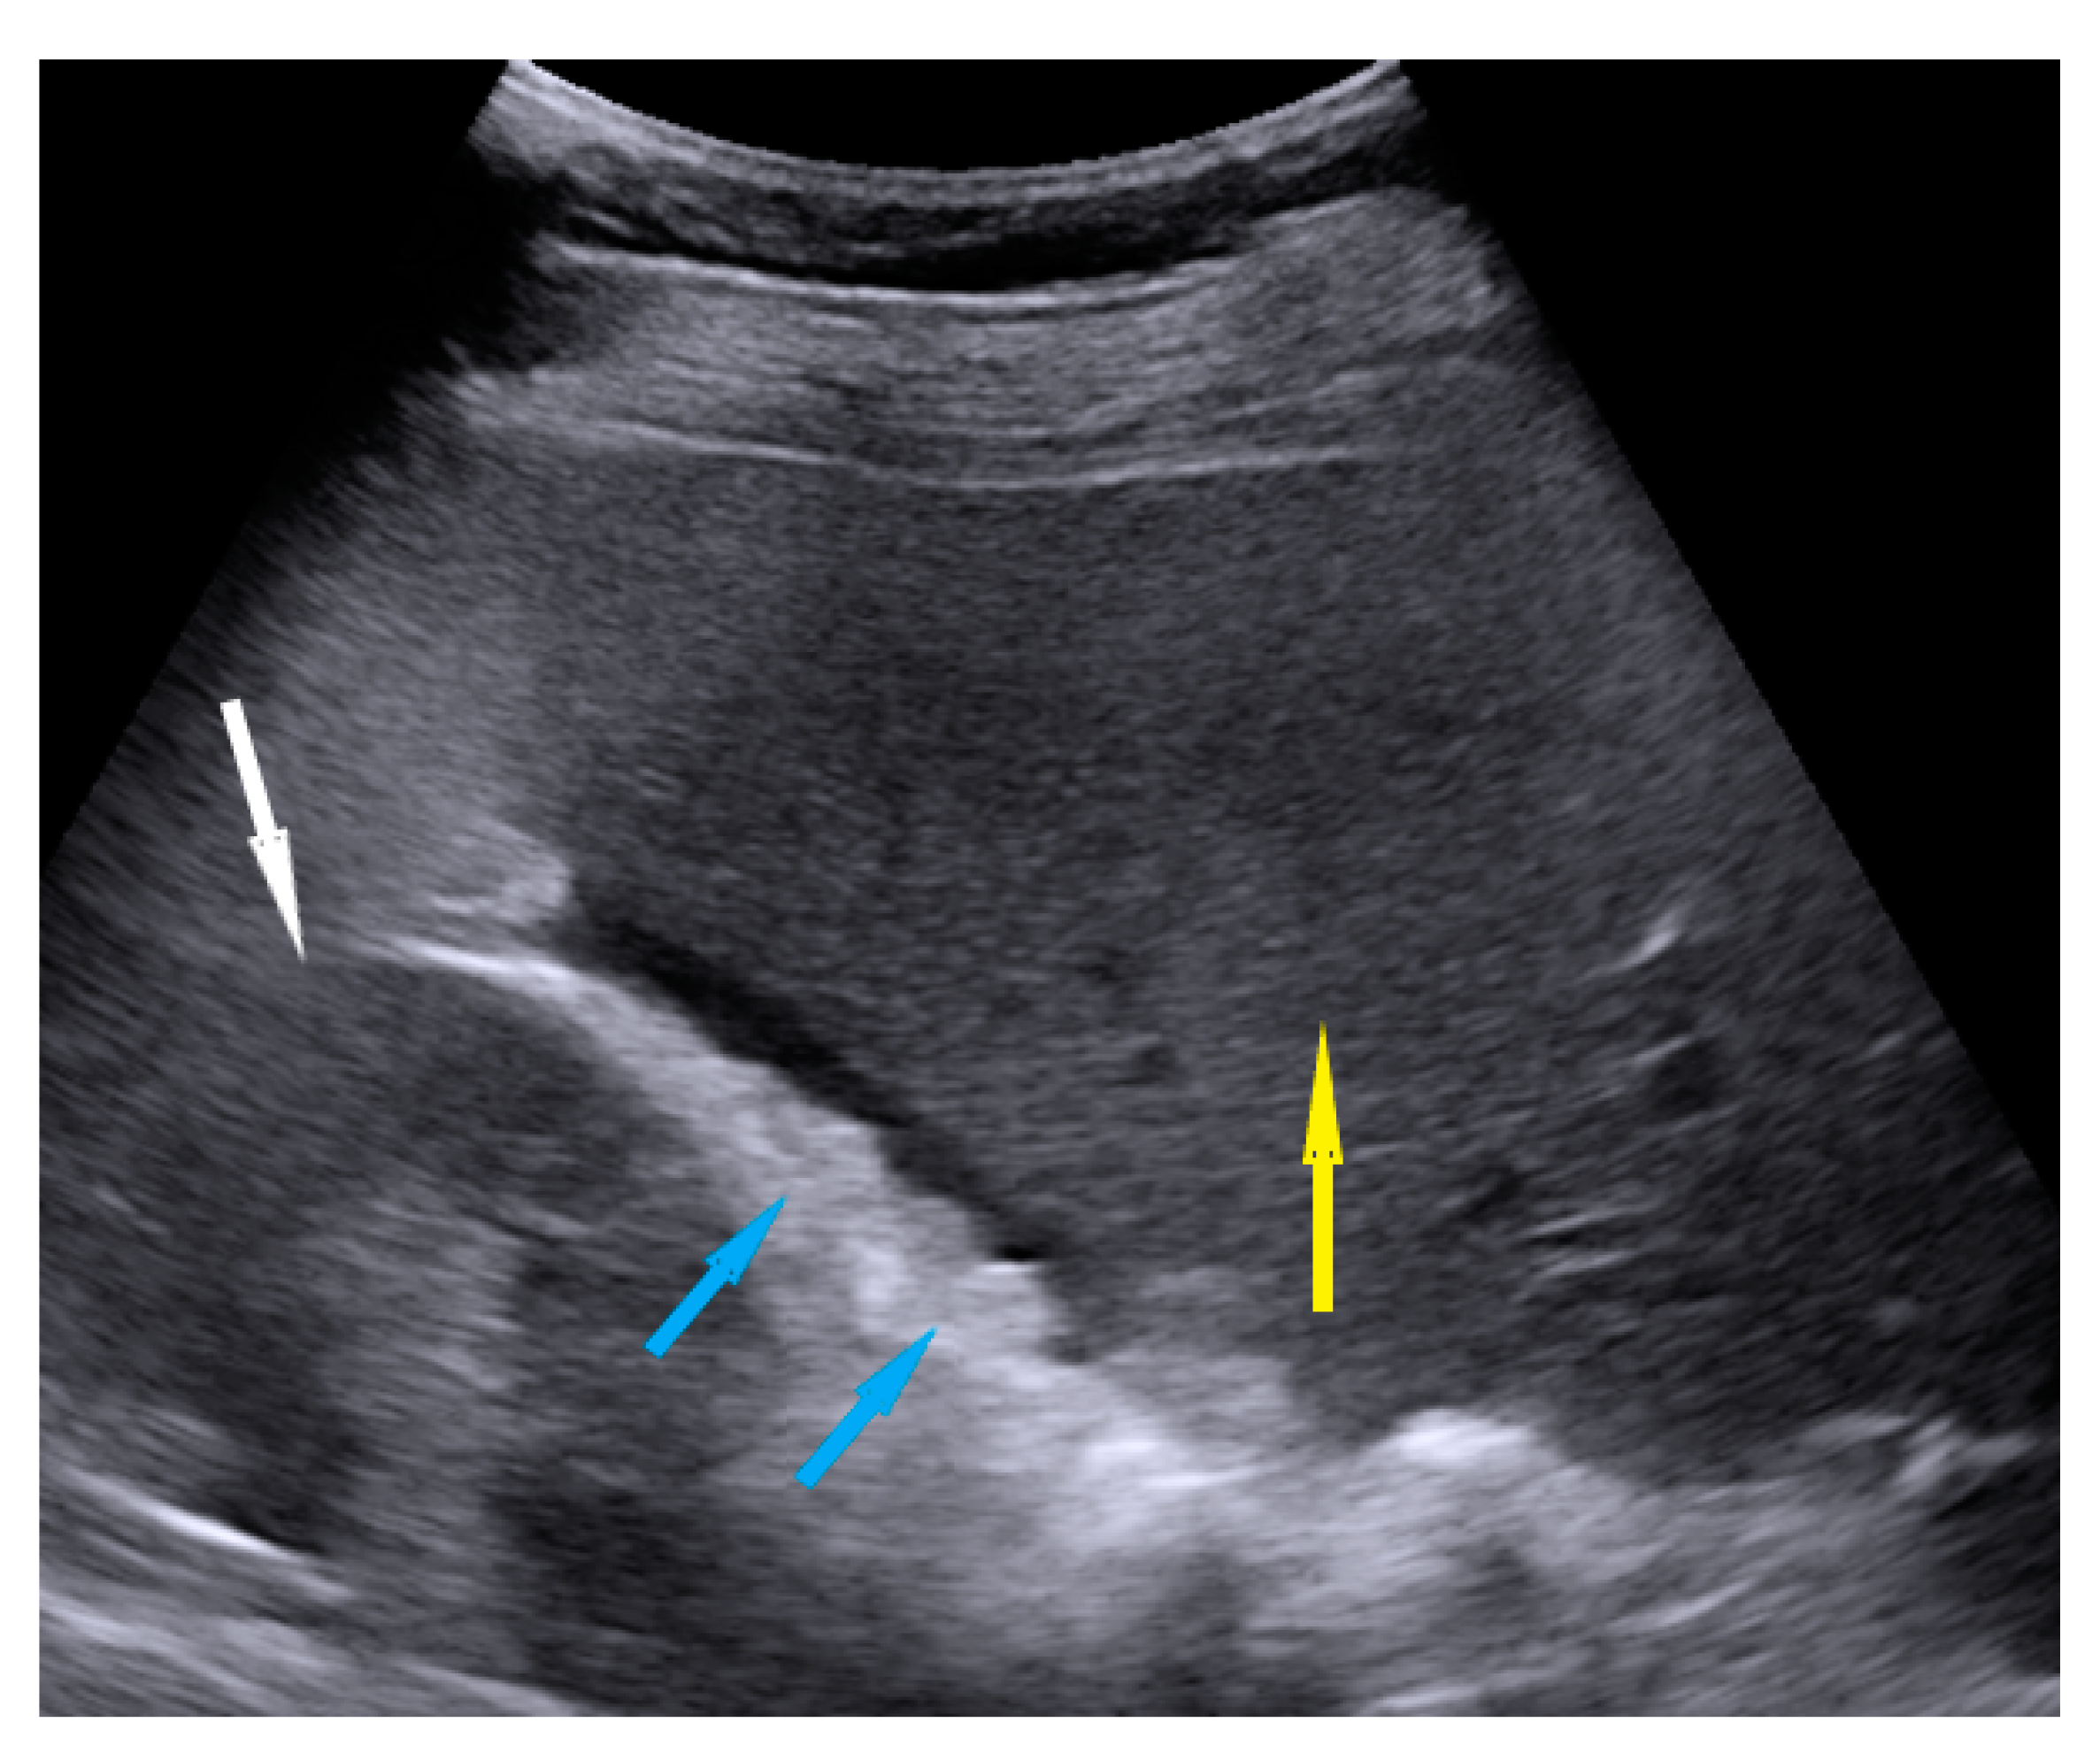

| Omentum | Focal infiltration of omentum: hypoechogenic nodules with discrete vascularization. Diffuse infiltration: omental cake appears as a nodular, perfuse, and non-peristaltic tumor that is located between the anterior abdominal wall and bowel loops. | Figure 1 | Video S1 |

| Small bowel mesentery root | Involvement is suspected when bowel loops have poor mobility and are “fixed together” in the dynamic ultrasound examination with a cauliflower-like image. | Figure 2 | Video S2 |

| Peritoneum, abdomen | Abdomen carcinomatosis manifest as hypoechogenic lesions over the peritoneal surface of the paracollic gutters or internal abdominal wall. | Figure 3 | Video S3 |

| Peritoneum, pelvis | Pelvic carcinomatosis manifests as hypoechogenic lesions over the peritoneal surface of the pelvic wall: laterally, in the pouch of Douglas (no rectum involvement) or the bladder in the uterine serosa. | Figure 4 | Video S4 |